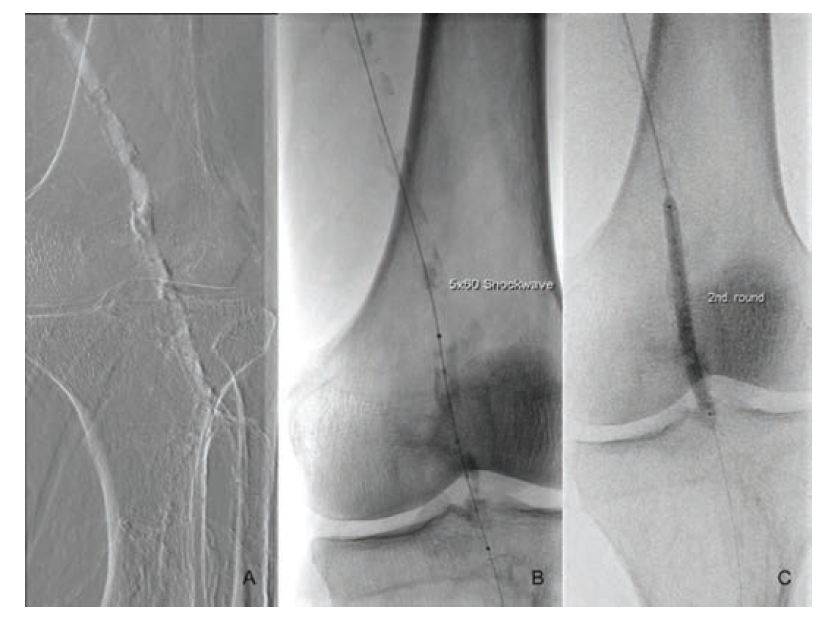

Under local anesthesia, left antegrade femoral arterial access was obtained using ultrasound guidance. After the insertion of a short 6 Fr arterial sheath (Terumo), a diagnostic angiogram was performed using the Angiodroid carbon dioxide (CO2) injector (San Lazzaro di Savena, Italy). This confirmed the preprocedural duplex ultrasound findings (Figure 1). A Choice PT 0.014 floppy wire (Boston Scientific) and a Quick-Cross support catheter (Phillips) were used to cross the lesion. After crossing the lesion, a vessel preparation with endovascular lithoplasty (Shockwave Medical, Fremont, US) was performed using a 5 × 60 mm catheter inflated to 4 atm and activated. After delivering 30 pulses, the balloon was inflated to the reference vessel diameter for an additional 120 seconds. The lithoplasty was activated an additional 6 times after repositioning of the catheter in order to treat the entire lesion from “healthy to healthy,” delivering a total of 180 pulses. An antirestenotic therapy with a drug coated balloon (DCB) (5 ×120 mm, In.Pact Admiral, Medtronic) was applied following the plaque modification. The final angiography did not show any residual stenosis, local dissection, or distal embolization. The procedure was completed with the use of 10 mL contrast medium, and the patient was discharged the following day.